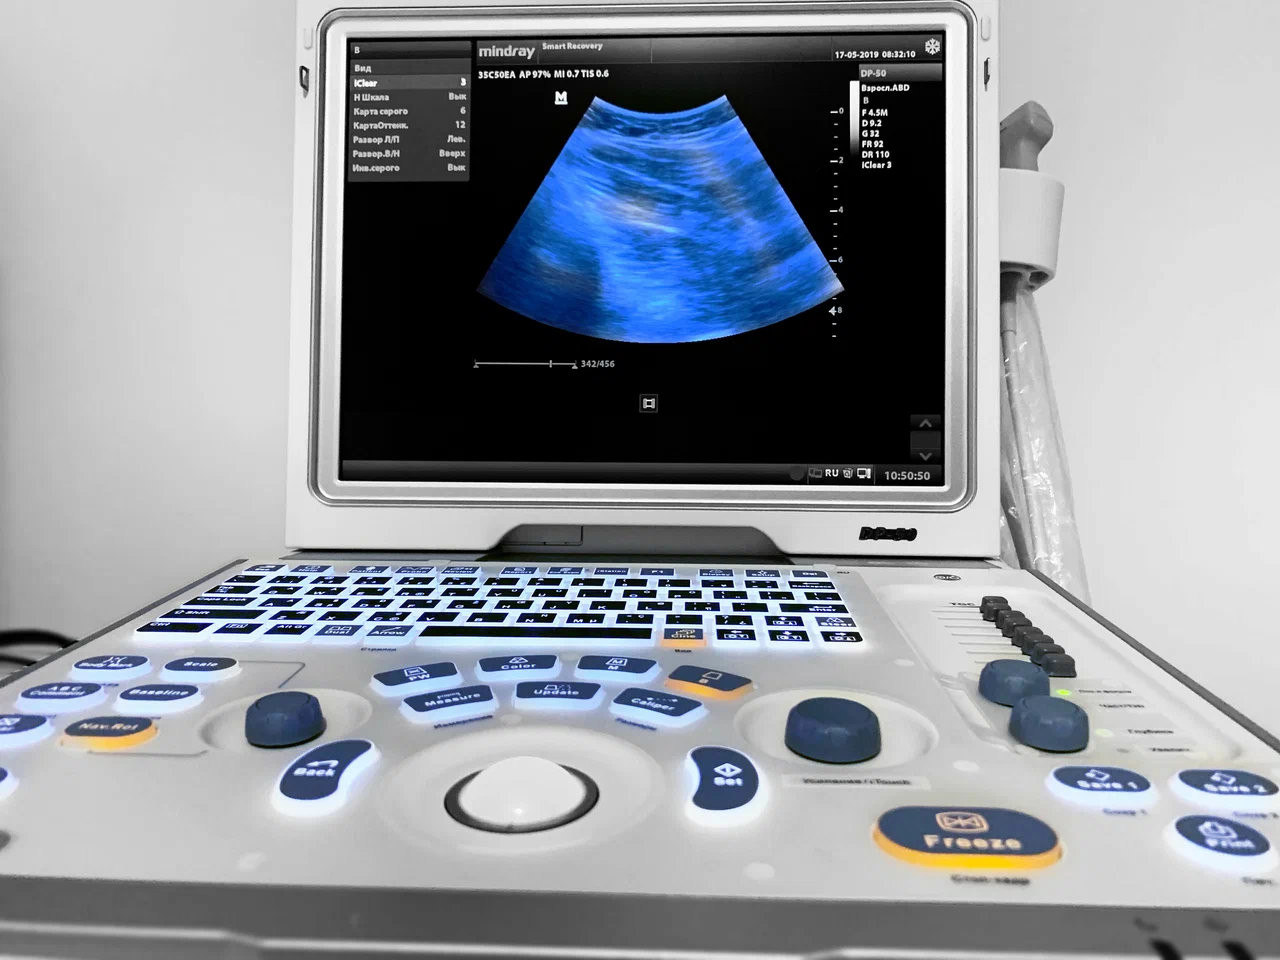

Ультразвуковое исследование

УЗИ-диагностика травм и контроль восстановления

Ультразвуковая диагностика (УЗИ) — это современный, безопасный и высокоинформативный метод исследования, который широко применяется для диагностики травм, заболеваний и контроля восстановления опорно-двигательного аппарата и внутренних органов. В спортивной медицине и медицине активного образа жизни УЗИ используется не только для постановки диагноза, но и для динамического наблюдения за состоянием тканей на фоне лечения и физических нагрузок.

Современные технологии УЗИ в Smart Recovery

Диагностика травм и функциональных изменений требует применения высокоточного оборудования. В клинике используется универсальный ультразвуковой сканер Samsung V7-RUS, разработанный компанией Samsung Medison Co., Ltd.

Процесс проведения ультразвуковой диагностики максимально комфортен для пациента. На кожу в области исследования наносится специальный гель, который улучшает контакт с датчиком. Датчик, подключённый к сканеру, посылает ультразвуковые волны и принимает отражённые сигналы, создавая изображение внутренних органов на экране. Вся процедура обычно занимает от 10 до 30 минут и не вызывает дискомфорта. Результаты исследования зачастую можно получить сразу после окончания сеанса.